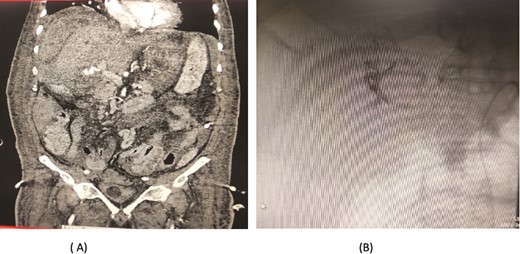

A 66-year-old male underwent an extended cholecystectomy with bile duct excision and Roux-en-Y hepaticojejunostomy for suspected gallbladder carcinoma. However, the histopathological examination revealed xanthogranulomatous cholecystitis. Postoperative patient develops anastomotic site leakage so was discharged with abdominal drain. On the 9th postoperative day, during follow-up for bile leak with an abdominal drain in situ, a contrast-enhanced CT scan of the abdomen identified a pseudoaneurysm at the bifurcation of the gastroduodenal artery and proper hepatic artery. Angioembolization was performed using two coils and 50% glue. The abdominal drain was subsequently removed, and the patient recovered without further complications, doing well at follow-up (Fig. 4).

Case 4. (A) CT scan – pseudoaneurysm at bifurcation of gastroduodenal artery and proper hepatic artery. (B) Embolization of gastroduodenal artery and proper hepatic artery.